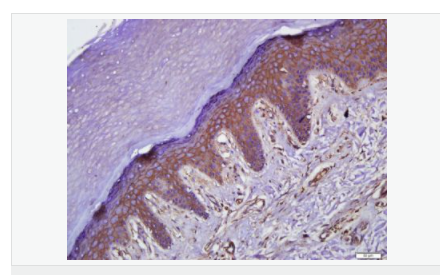

| 英文名稱 | Occludin |

| 中文名稱 | 緊密連接蛋白抗體 |

| 別 名 | Occludin, Occludin-1; Occludin1; Occludin 1; FLJ08163; BLCPMG; FLJ18079; FLJ77961; FLJ94056; MGC34277; Occludin; OCLN; OCLN_HUMAN; Tight junction protein occludin. |

| 產(chǎn)品應用 | WB=1:500-2000 ELISA=1:5000-10000 IHC-P=1:100-500 IHC-F=1:100-500 Flow-Cyt=1μg/Test ICC=1:100 IF=1:100-500 (石蠟切片需做抗原修復) not yet tested in other applications. optimal dilutions/concentrations should be determined by the end user. |

| 產(chǎn)品介紹 | This gene encodes an integral membrane protein which is located at tight junctions. This protein may be involved in the formation and maintenance of the tight junction. The possibility of several alternatively spliced products has been suggested but the full nature of these products has not been described. [provided by RefSeq]. Function: May play a role in the formation and regulation of the tight junction (TJ) paracellular permeability barrier. Subunit: Interacts with TJP1/ZO1 and with VAPA. Subcellular Location: Membrane; Multi-pass membrane protein. Cell junction, tight junction. Tissue Specificity: Localized at tight junctions of both epithelial and endothelial cells. Highly expressed in kidney. Not detected in testis. Post-translational modifications: Phosphorylated upon DNA damage, probably by ATM or ATR. Dephosphorylated by PTPRJ. May be phosphorylated by PKC during translocation to cell-cell contacts. Similarity: Belongs to the ELL/occludin family. Contains 1 MARVEL domain. SWISS: Q16625 Gene ID: 100506658 Database links: Entrez Gene: 18260 Mouse Entrez Gene: 100506658 Human Omim: 602876 Human SwissProt: Q16625 Human SwissProt: Q61146 Mouse Unigene: 592605 Human Unigene: 4807 Mouse Unigene: 31429 Rat Important Note: This product as supplied is intended for research use only, not for use in human, therapeutic or diagnostic applications. |